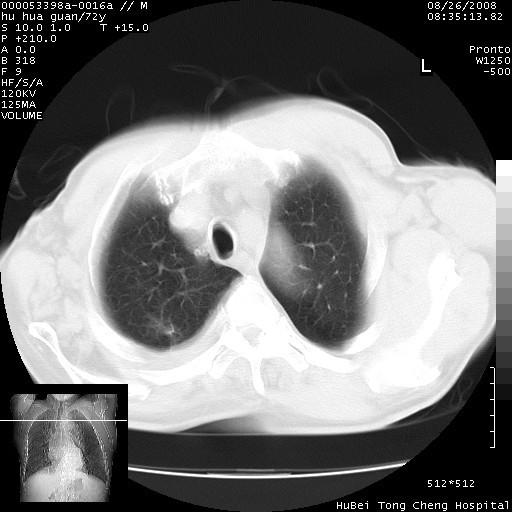

标题: CT15582:M,72Y。请老师帮分析胸部病变。 [打印本页]

标题: CT15582:M,72Y。请老师帮分析胸部病变。

可以明确的说。肯定不是主动脉夹层破裂出血!考虑为淋巴瘤或间叶组织来源的恶性肿瘤可能性大。右肺小结节建议薄层观察,如能发现恶性征象,那椎前改变就考虑为转移所致。至于双侧少量胸水乃静脉血回流受阻所致。

图像及窗宽窗位均不理想。周围性肺癌/胸腔积液/纵隔积液。

1、右肺周围性肺癌、胸腔积液(双)

1、右上肺结节病变,肺泡癌不除外,请随诊;左下肺近后纵隔病变,考虑纵隔型肺癌侵犯大血管可能;

2、右下肺背段少许炎症,双侧胸腔积液,右下肺纤维索条。

降主动脉前移位,后纵隔占位

后纵隔占位,降主动脉前移位;双侧胸腔积液;应排外食管病变侵犯血管可能;